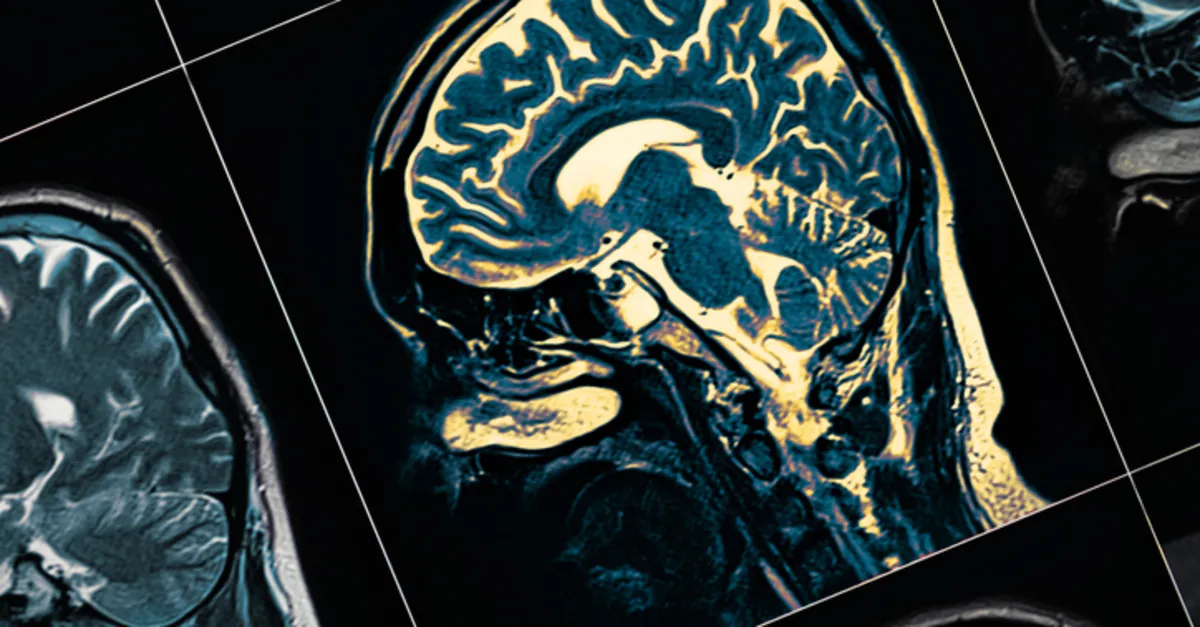

Demans, hatırlama, düşünme, problem çözme veya karar verme yeteneğinin kaybıyla birlikte azalan bilişsel işlevleri bir araya getirir. Hastalığın ilerleyen dönemlerinde günlük aktiviteleri engelleyecek bir noktaya ilerleyebilir. Demans, geniş bir terimdir ve bunamaya dair birçok hastalığı tanımı içerisine alır.

Güney Avustralya Üniversitesi'nden dünya çapında yapılan bir çalışma, yeni genetik araştırmalar, bunama ve D vitamini arasında doğrudan bir bağlantı keşfedildi.

• Düşük D vitamini seviyeleri, daha düşük beyin hacmi ve buna bağlı olarak artan bunama ve felç riski ile ilişkilendirildi.

• Genetik analizler, D vitamini eksikliği ve bunamanın nedensel etkisini destekledi.

• Bazı popülasyonlarda, herkesin normal D vitamini seviyelerine (50 nmol/L) yükseltilmesiyle demans vakalarının %17 kadar önlenebileceği keşfedildi.

Demans, bilişsel işlevde bozulmaya yol açan kronik veya ilerleyici bir sendromdur. Küresel olarak, her yıl 10 milyon yeni vaka teşhis edilirken, 55 milyondan fazla insan ise demans hastasıdır.

Ulusal Sağlık ve Tıbbi Araştırma Konseyi tarafından desteklenen genetik çalışma, Birleşik Krallık Biobank'tan 294.514 katılımcıdan alınan verileri analiz ederek düşük D vitamini (25 nmol/L) düzeylerinin etkisini ve bunama ve felç riskini inceledi.

Doğrusal Olmayan Mendel randomizasyonu (MR) (değiştirilebilir bir maruziyetin hastalık üzerindeki nedensel etkisini incelemek için genlerde ölçülen varyasyonu kullanma yöntemi) nörogörüntüleme sonuçları, demans ve felç için altta yatan nedenselliği test etmek için kullanıldı.

Kıdemli araştırmacı ve UniSA'nın Avustralya Hassas Sağlık Merkezi Direktörü Profesör Elina Hyppönen, bulguların demansın önlenmesi için önemli olduğunu ve D vitamini eksikliğinin ortadan kaldırılması ihtiyacının önemli olduğunu söylüyor.

Profesör Hyppönen, D vitamini, beyin sağlığı da dahil olmak üzere yaygın etkileri için giderek daha fazla bir hormon öncüsü olarak nitelendirildiğinin belirtiliyor.

Çalışmanın çok düşük D vitamini düzeylerinin demans ve felç riskleri üzerindeki etkisinin geniş bir popülasyonda sağlam genetik analizler kullanarak inceleyen ilk çalışma.

D vitamini eksikliğinin nispeten yaygın olduğu düşünüldüğünde gerçekten önemli bir veri elde ettiklerini de göz önünde bulundurmak gerekiyor.

Profesör Hyppönen, demansın hem bireyleri hem de aileleri büyük bir zorluğa sürükleyen ilerleyici ve zayıflatıcı bir hastalık olduğunu belirtiyor.

Herkesin ciddi şekilde D vitamini eksikliği yaşamasını engelleyerek daha fazla fayda edilebileceğini, binlerce kişinin sağlık sürecini ise değiştirebileceklerini belirtiyor.